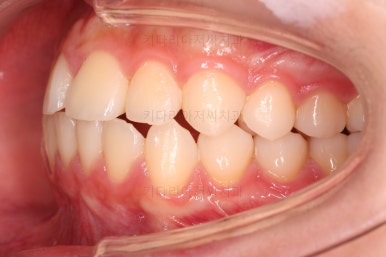

초진 시의 다른 부위들 사진입니다.

약간의 주걱턱 느낌에 약간의 돌출감, 전반적인 치열의 가지런한 느낌은 나쁘진 않았지만 약간의 불량한 교합상태였어요.

다른 부분은 크게 바꾸지 말고 약간의 교합 조절과 어금니 치료에 초점을 맞춰서 교정치료 계획을 잡았습니다.